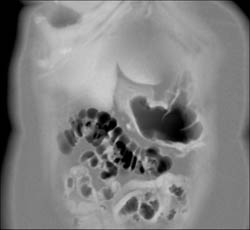

Diagnosis

Antral Cancer